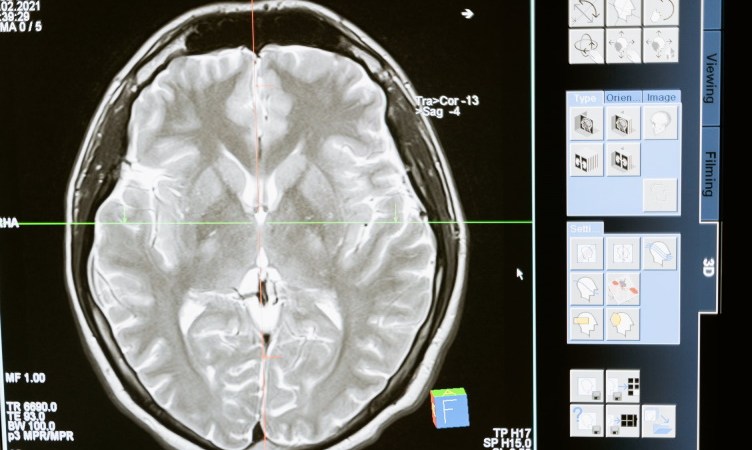

Ein varslar frå helseføretaket Vitalité Network i den kanadiske provinsen New Brunswick fortel at legar er lamslegne over den urovekkjande førekomsten av ein ukjent, men aggressiv hjernesjukdom som i hovudsak råkar unge. Symptoma er blant anna tap av kognitive funksjonar, hallusinasjonar og muskelsvinn. Dei to fyrste er vanlege ved enkelte former for demens, men er òg å finne blant personar med Creutzfeldt-Jakob-sjukdom, ein dødeleg og uhelbredeleg prionsjukdom. Andre symptom inkluderer åtferdsendringar, søvnforstyrringar i form av insomni (søvnløyse), vekttap og sikling. Eit anna symptom er ataksi, manglande evne til å bevege seg. Dette påverkar mellom anna gå-evne.

Ein frykta prionsjukdom som forårsakar total søvnløyse, er den sjeldne, genetiske lidinga Dødeleg familiær søvnløyse (på engelsk Fatal familial insomnia). Andre symptom er nettopp òg raskt fall i kognitive evner, hallusinasjonar og demens. I sjukdommens seinare stadium førekjem det òg betydeleg vekttap. Lidinga er arveleg, men kan òg oppstå spontant. Symptoma skjer fordi prionar (misfalda proteinar) øydelegg hjernecellene i talamus, som blant anna regulerer overgangen frå vaken til sovande tilstand. Personar med lidinga er ikkje berre torturert av fullstendig søvnløyse, men har òg øydelagt temperaturregulering, noko som fører til høg feber og at heile kroppen rett og slett går i høggir (engelsk sympathetic overdrive). Denne tilstanden er ein av årsakene til vekttapet i slutten av sjukdommen. Dei døyr til slutt plutseleg på grunn av hjerneskadane som akkumulerer seg. Som andre prionsjukdommar, påverkar hjerneskadane gå-evne slik at dei til slutt hamnar i rullestol.

Ulikt dødeleg søvnløyse og Creutzfeldt-Jakob, som hovudsakleg råkar middelaldrande, råkar denne sjukdommen unge. Og ulikt dei to nemnde prionsjukdommane, ser denne hjernesjukdommen ut til å vere smittsam. Den kanadiske helsetenesta har rapportert om minst ni tilfelle der to nært tilknytte personar som ikkje var i slekt har utvikla symptom. Her kan ein derimot òg snakke om miljøfaktorar. Er det noko i New Brunswick-provinsen som forårsakar denne urovekkjande sjukdommen?